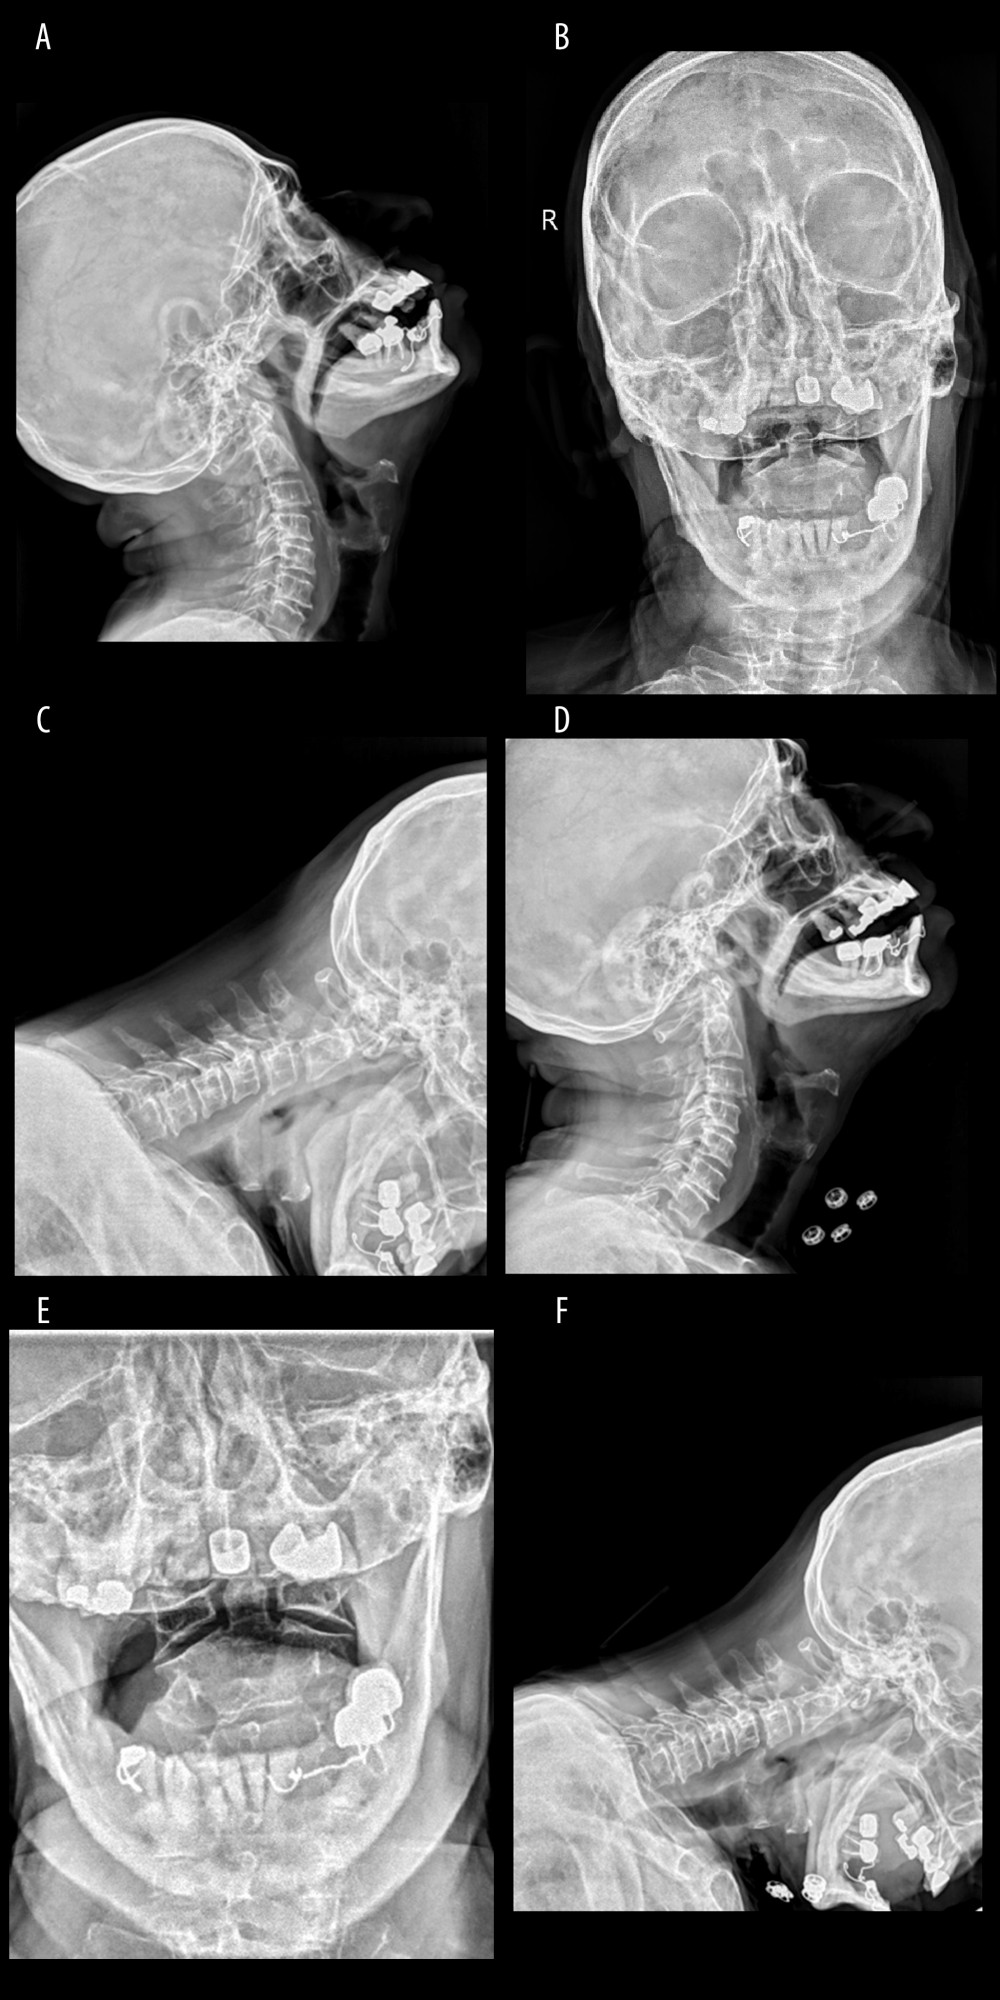

Atlantoaxial Joint Subluxation

Atlantoaxial Subluxation - Musculoskeletal and Connective Tissue Disorders - Merck Manuals Professional Edition Atlanto-axial subluxation | Radiology Reference Article | Radiopaedia.org Atlantoaxial Instability (Atlantoaxial Subluxation): Practice Essentials, Background, Epidemiology Atlantoaxial Instability - Spine - Orthobullets Diagnosis and Treatment of Atlantoaxial Dislocation & Atlantoaxial Subluxation in India | Dr Sumit Sinha Atlantoaxial Joint Subluxation